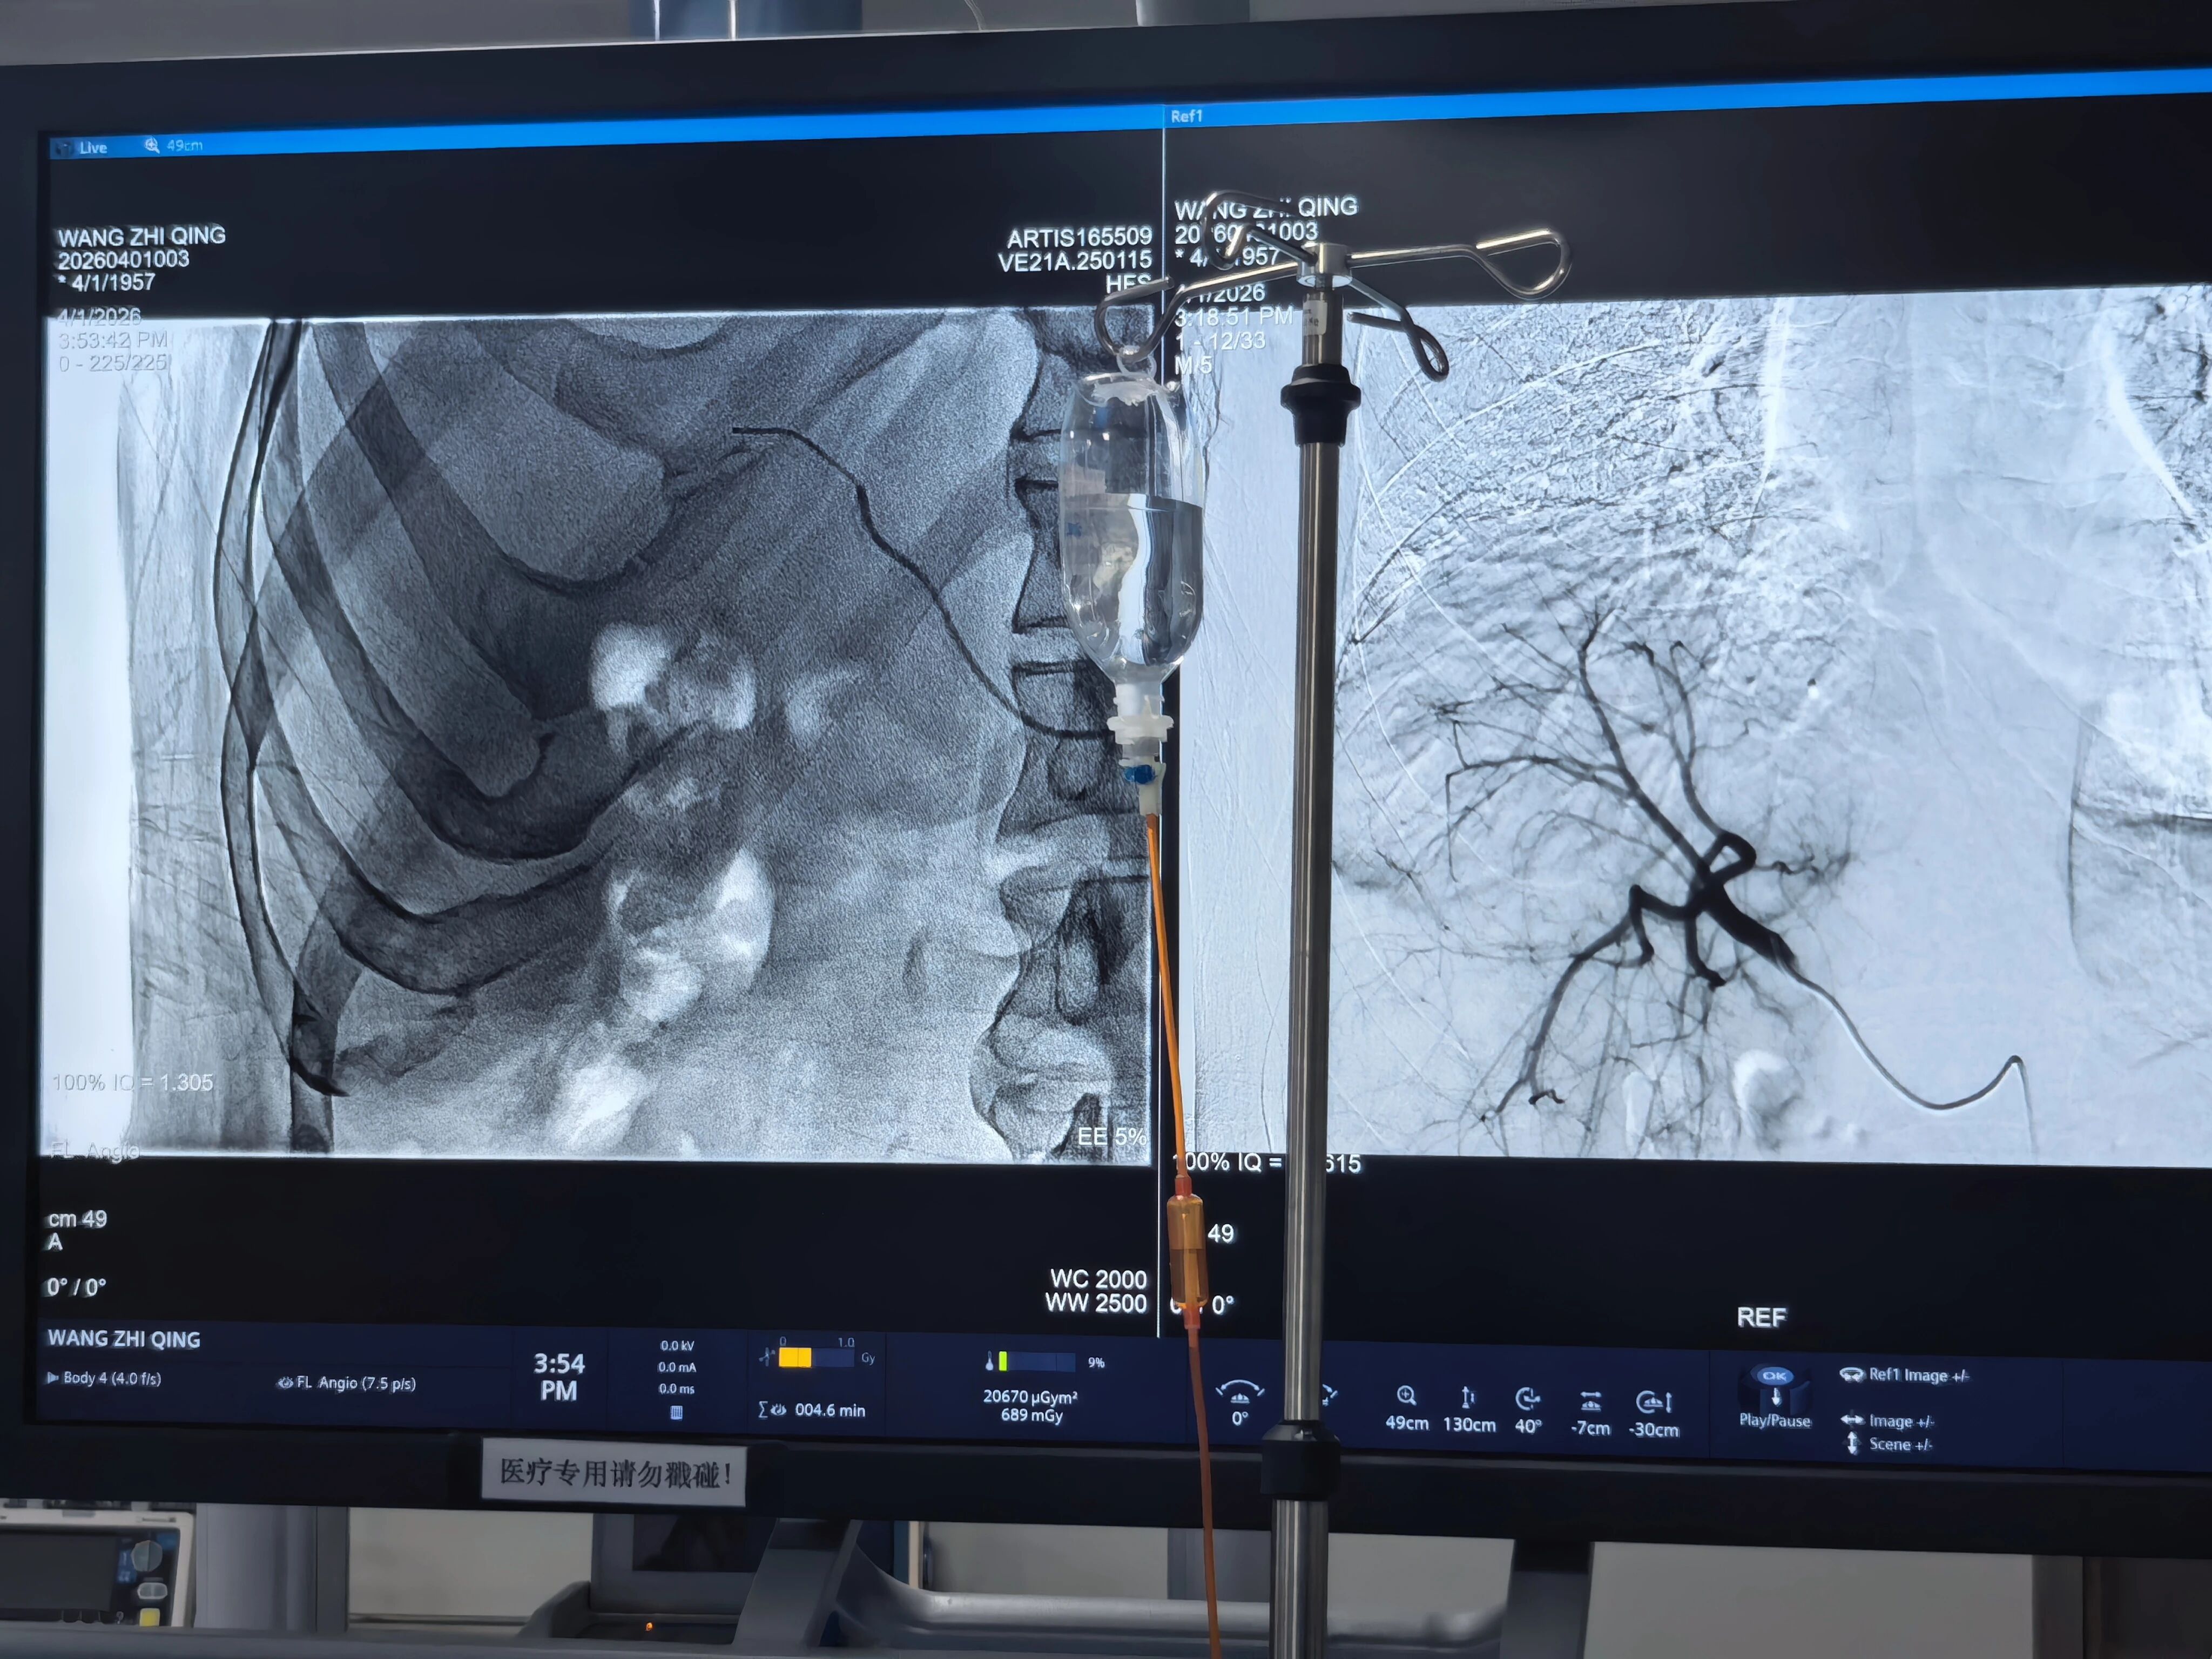

此次接受治疗的患者为男性,69岁,确诊肝右叶巨大肿瘤、晚期,因肿瘤体积大、位置特殊,已失去常规手术机会。经MDT团队全面评估,认为钇90微球是最适合的个体化方案。手术在数字减影血管造影机(DSA)引导下完成,专家团队经股动脉穿刺,将数百万个携带放射性核素的树脂微球精准送达肿瘤供血动脉 。微球如同“体内隐形手术刀”,均匀沉积于肿瘤内部,持续释放高能量β射线,辐射半径仅2.5毫米,实现对癌细胞的精准“全覆盖”杀灭,同时最大程度保护正常肝组织。